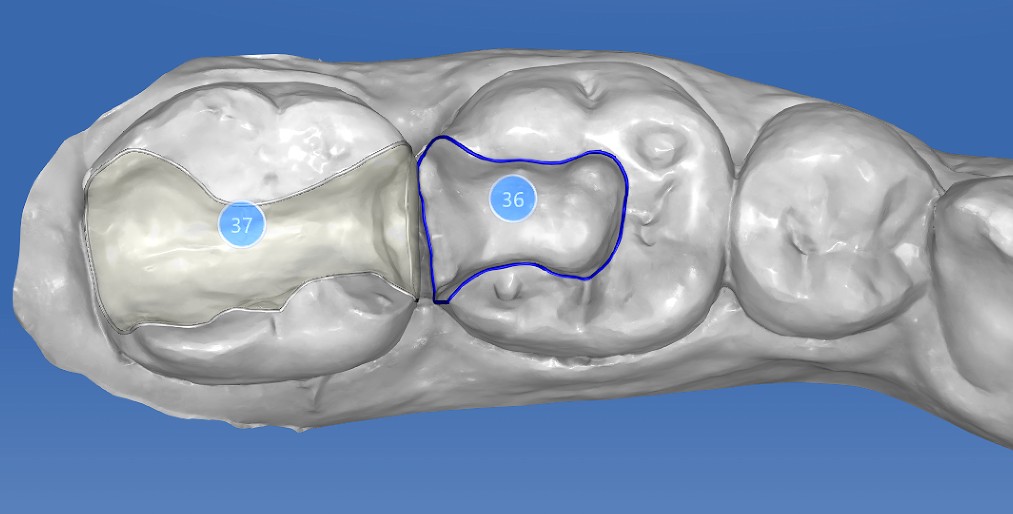

口腔检查时,会经常遇到以前补的银汞合金边缘变色,探有卡顿,形成了继发龋坏,建议重新充填或者瓷嵌体修复;瓷嵌体修复技术,可以非常好的恢复牙体形态和非常密合的边缘,色泽也非常逼真;我们采用CEREC(德国瓷睿刻)椅旁加工技术,达到最佳修复效果!